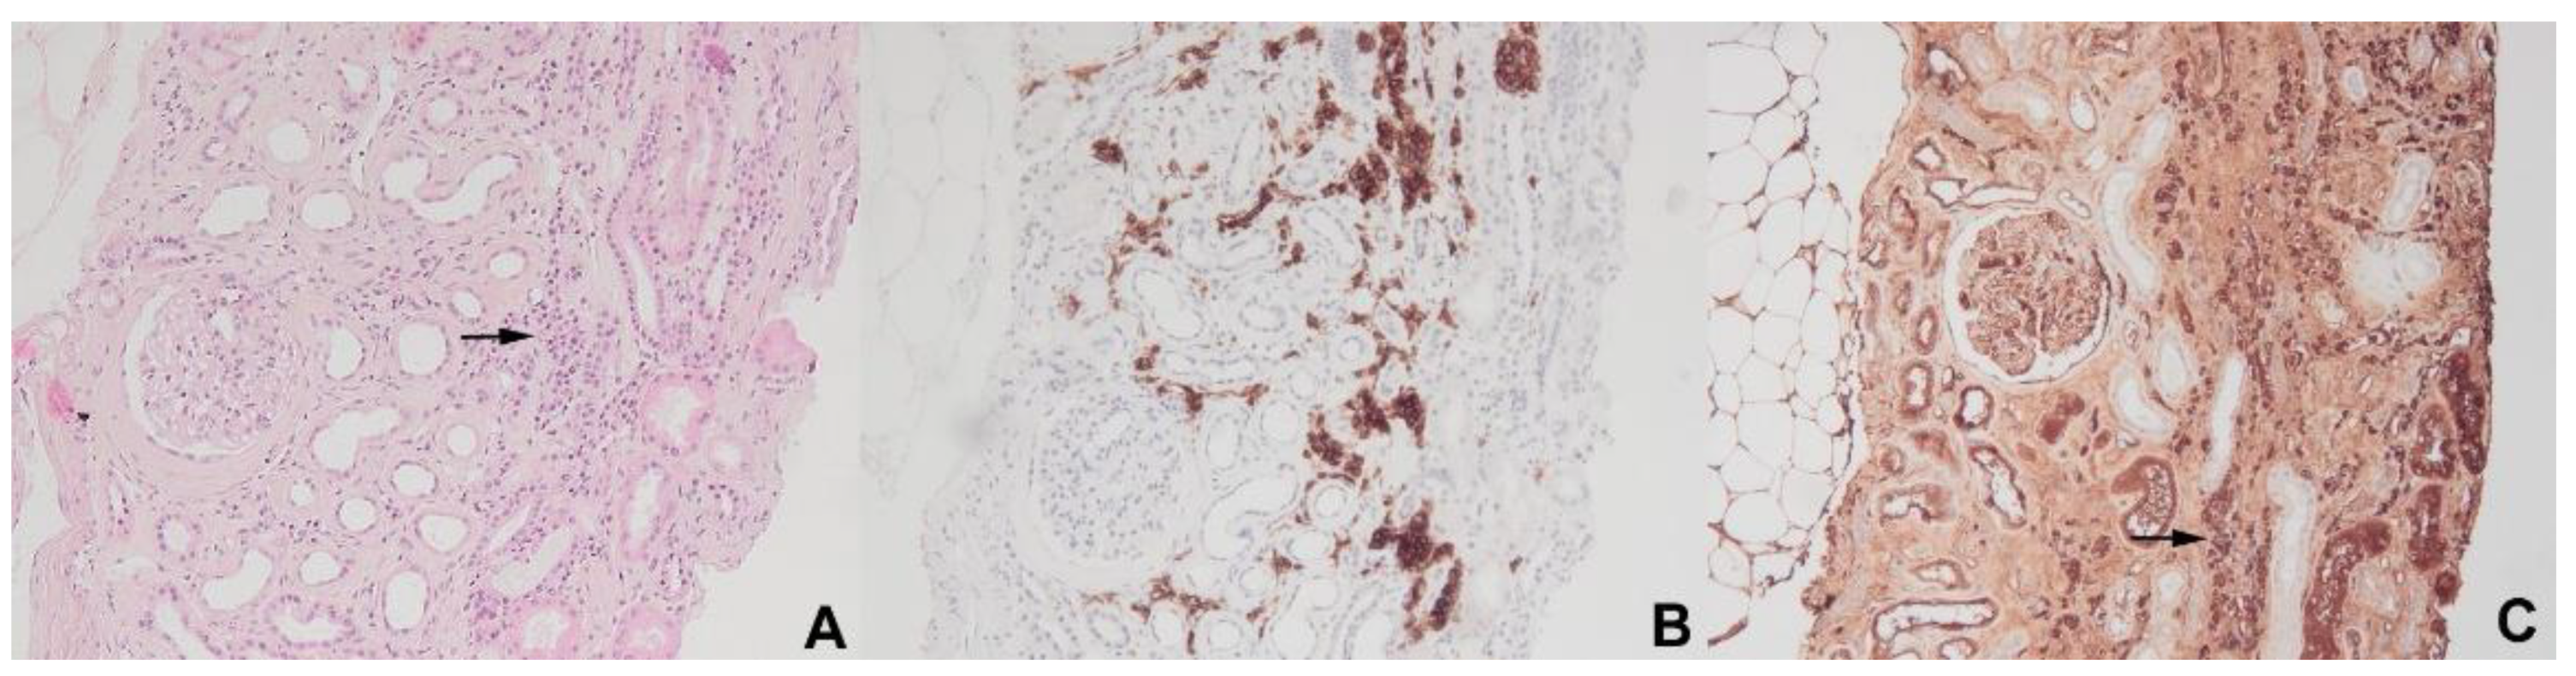

- Javaugue, V.; Debiais-Delpech, C.; Nouvier, M.; Gand, E.; Chauvet, S.; Ecotiere, L.; Desport, E.; Goujon, J.-M.; Delwail, V.; Guidez, S.; et al. Clinicopathological spectrum of renal parenchymal involvement in B-cell lymphoproliferative disorders. Kidney Int. 2019, 96, 94–103. [Google Scholar] [CrossRef] [PubMed]

- Corlu, L.; Rioux-Leclercq, N.; Ganard, M.; Decaux, O.; Houot, R.; Vigneau, C. Renal dysfunction in patients with direct infiltration by B-cell lymphoma. Kidney Int. Rep. 2019, 4, 688–697. [Google Scholar] [CrossRef] [PubMed]